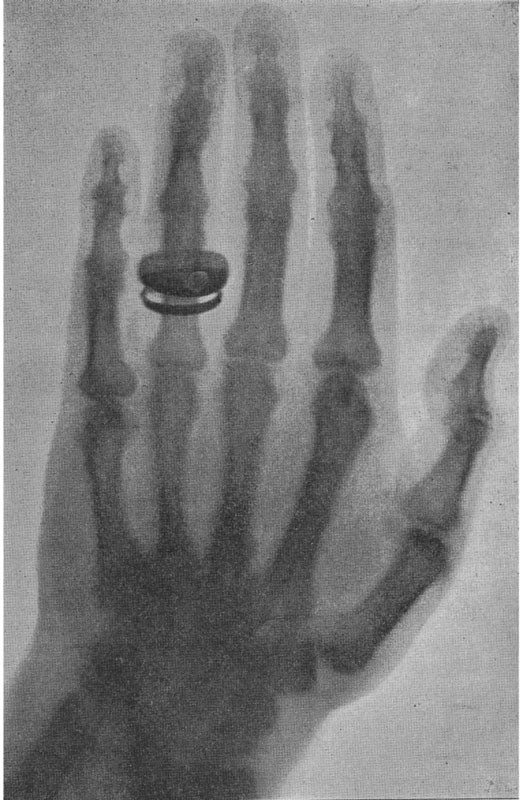

December 1895

Wilhelm Röntgen, a physics professor at the University of Würzburg, published his discovery of x-rays in the Sitzungsberichte der Wurzburger Physikalisch-Medicinischen Gesellschaft, the Meeting Reports of the Wurzburg Physical-Medical Society. Röntgen named the rays “X” to indicate the unknown nature of the radiation. In 1901 Röntgen received the first Nobel Prize in physics for his discovery.